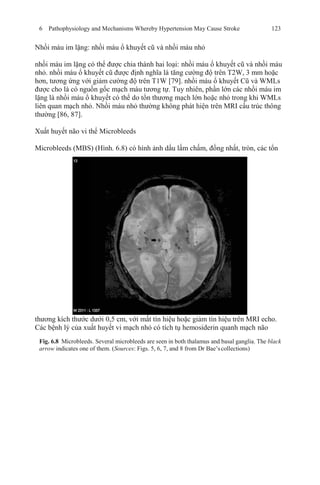

24. Perry Jr HM, Smith WM, McDonald RH, et al. Morbidity and mortality in the Systolic

Hypertension in the Elderly Program (SHEP) pilot study. Stroke. 1989;20:4–13.

25. The SHEP Cooperative Study Group. Prevention of stroke by antihypertensive drug treatment